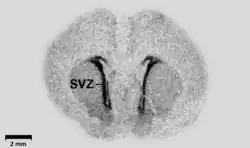

![]() La ZSV teñida en oscuro en cerebro de rata. | ||

La zona subventricular (ZSV o SVZ por sus siglas en inglés) es un término utilizado para describir tanto el tejido embrionario como el tejido neuronal adulto localizado bajo los ventrículos laterales del sistema nervioso central en los vertebrados. En la etapa embrionaria la ZSV refiere a una zona secundaria de proliferación que contiene células progenitoras neurales que se dividen para producir neuronas en el proceso llamado neurogénesis.[2] Las células madre neurales primarias del encéfalo y la médula espinal, llamadas células gliales radiales, residen en la zona ventricular (ZV) (llamada así porque la ZV delimita los ventrículos en el desarrollo).[3] Durante el desarrollo, la ZSV y la ZV de la corteza cerebral en el telencéfalo dorsal son tejidos transitorios que no existen en el adulto.[3] En cambio, la ZSV del telencéfalo ventral persiste a lo largo de la vida.

La ZSV adulta es una estructura apareada del encéfalo que se sitúa a a lo largo de las paredes laterales de los ventrículos laterales.[4] Está compuesta de cuatro capas de grosor, densidad y composición celular variable.[5] Junto con el giro dentado del hipocampo la ZSV es uno de los dos sitios donde se ha encontrado neurogénesis adulta en el cerebro de mamíferos adultos.[6] Las células generadas en la ZSV migran a través de la vía rostral migratoria hasta alcanzar el bulbo olfatorio.